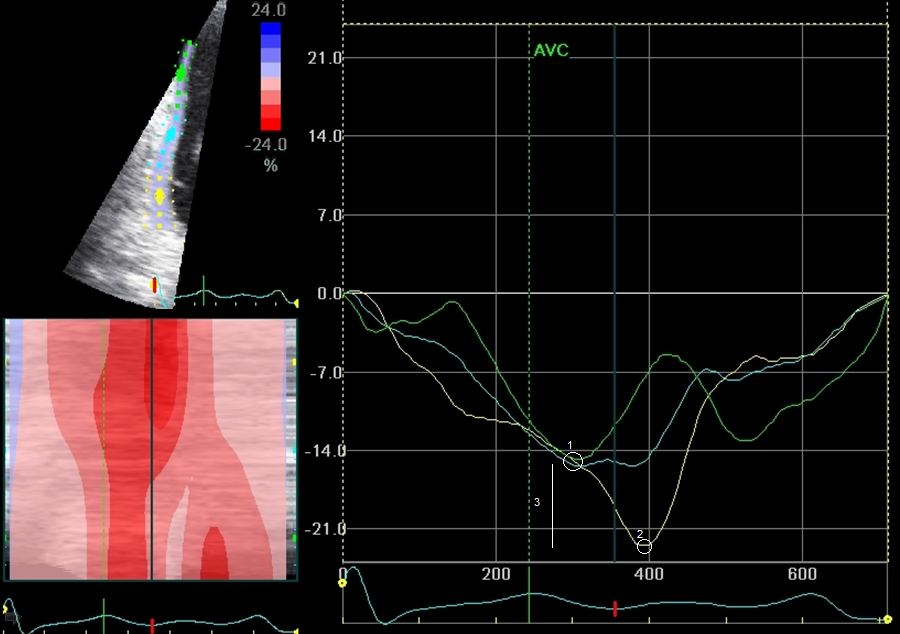

Συγγραφείς: S. Koretskiy N., O. Drapkina M., F. Shukurov B., D. Vasiliev K., С. Корецкий Н., О. Драпкина М., Ф. Шукуров Б., Д. Васильев К.

Πηγή: Rational Pharmacotherapy in Cardiology; Vol 15, No 6 (2019); 813-819 ; Рациональная Фармакотерапия в Кардиологии; Vol 15, No 6 (2019); 813-819 ; 2225-3653 ; 1819-6446

Θεματικοί όροι: multimodal stress echocardiography, semi-supine bicycle, speckle tracking, three-dimensional visualization, coronary heart disease, multivessel coronary heart disease, мультимодальная стресс-эхокардиография, «лежачий» велоэргометр, отслеживание пятнистых структур, трехмерная визуализация, ишемическая болезнь сердца, многососудистое поражение коронарных артерий

Περιγραφή αρχείου: application/pdf

Relation: https://www.rpcardio.com/jour/article/view/2073/1888; National Heart, Lung, and Blood Institute. Morbidity and Mortality: 2012 Chart book on cardiovascular, lung, and blood diseases. Bethesda, MD: National Institutes of Health; 2012.; Califf R. Importance of clinical measures of ischemia in the prognosis of patients with documented coronary artery disease. JACC. 1988;11:20-6. DOI:10.1016/0735-1097(88)90160-X.; Pradhan R., Chaudhary A., Donato A.A. Predictive accuracy of ST-depression during rapid atrial fibrillation on the presence of obstructive coronary artery disease. Am J Emerg Med. 2012;30:1042-7. DOI:10.1016/j.ajem.2011.06.027.; Task Force Members, Montalescot G., Sechtem U., Achenbach S., et al. 2013 ESC guidelines on the management of stable coronary artery disease: the Task Force on the management of stable coronary artery disease of the European Society of Cardiology. Eur Heart J. 2013;34:2949-3003. DOI:10.1093/eurheartj/eht296.; Nagel E., Lehmkuhl HB., Bocksch W., et al. Noninvasive diagnosis of ischemia-induced wall motion abnormalities with use of high-dose dobutamine stress-MRI: comparison with dobutamine stress echocardiography. Circulation. 1999;99:763-70. DOI:10.1161/01.cir.99.6.763.; Sicari R., Nihoyannopoulos P., Evangelista A., et al. Stress echocardiography expert consensus statement: European Association of Echocardiography (EAE) (a registered branch of the ESC). Eur J Echocardiogr. 2008;9:415-37. DOI:10.1093/ejechocard/jen175.; Ahmad M., Xie T., McCulloch M., et al. Real-time three-dimensionaldobutamine stress echocardiography in assessment stress echocardiography in assessment of ischemia: comparison with two-dimensionaldobutamine stress echocardiography. J Am Coll Cardiol. 2001;37:1303-9. DOI:10.1016/s0735-1097(01)01159-7.; Hodzic A., Chayer B., Wang D., et al. Accuracy of speckle tracking in the context of stress echocardiography in short axis view: An in vitro validation study. PLoS One. 2018;3:13. DOI:10.1371/journal.pone.0193805.; Reant P., Labrousse L., Lafitte S., et al. Experimental validation of circumferential, longitudinal, and radial 2-dimensional strain during dobutamine stress echocardiography in ischemic conditions.J Am Coll Cardiol. 2008;15:149-57. DOI:10.1016/j.jacc.2007.07.088.; Cerqueira M.D., Weissman N.J., Dilsizian V., et al. Standardized myocardial segmentation and nomenclature for tomographic imaging of the heart. A statement for healthcare professionals from the Cardiac Imaging Committee of the Council on Clinical Cardiology of the American Heart Association. Circulation. 2002;105:539-42. DOI:10.1161/hc0402.102975.; https://www.rpcardio.com/jour/article/view/2073